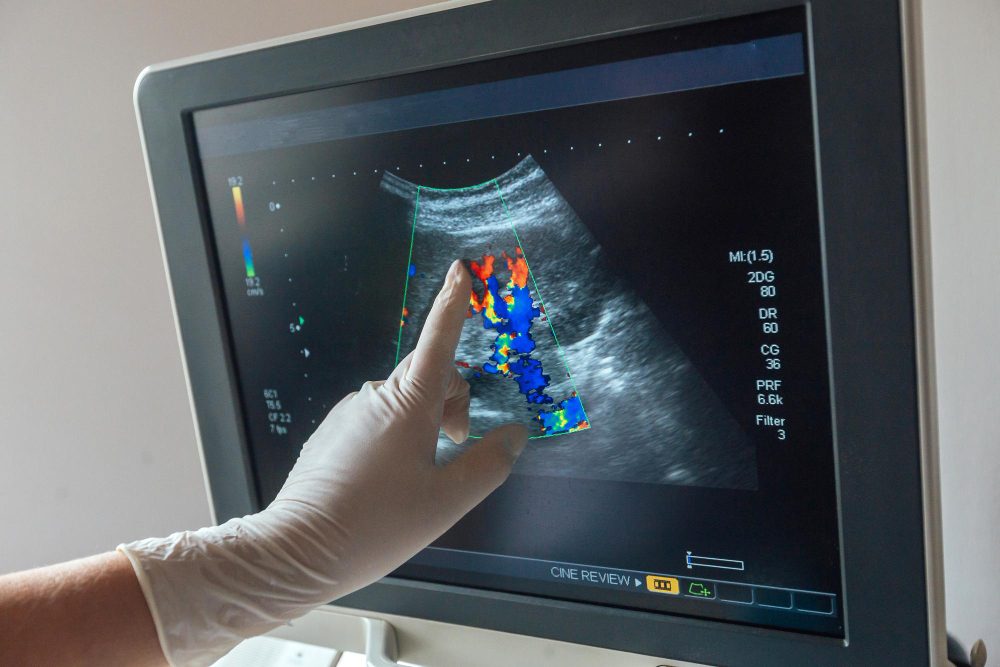

Допплерометрия плода

Допплерометрия плода – это метод ультразвуковой диагностики в гинекологии, направленный на изучение маточно-плацентарного кровотока. По особенностям кровообращения плаценты и пуповины врач может своевременно выявить сосудистые патологии беременной и гипоксию эмбриона.

УЗИ на 2 триместреОбследование проводится при помощи аппарата, генерирующего ультразвуковые колебания. Устройство работает в паре с датчиком, поддерживающим режим цветного допплеровского картирования. Это означает, что чувствительный прибор способен улавливать ультразвук, который отражается не от неподвижных объектов (как в случае с обычным УЗИ), а от циркулирующих клеток крови.

Компьютерная программа диагностического аппарата интерпретирует полученные данные, формирует цифровое изображение и выводит его на дисплей. Врач дает оценку результатам и сравнивает их с нормой допплерометрии в соответствии со сроком гестации.

ДопплерометрияГлавная задача диагностики – оценить, получает ли плод достаточное количество крови и кислорода для полноценного развития. Своевременное выявление сосудистых проблем позволяет как можно быстрее принять меры, чтобы избежать опасных последствий для матери и ребенка.